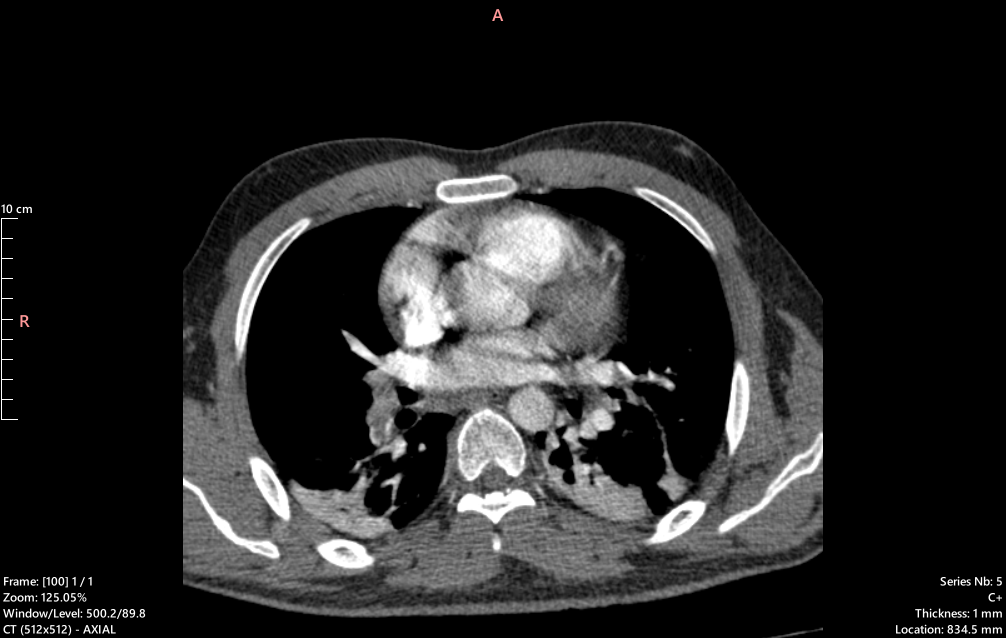

急性肺塞栓症(PE)は致死性の高い疾患であり、迅速な診断が求められます。 従来は造影CTが主流ですが、造影剤アレルギーや腎機能障害のある患者には適応が困難です。 本研究では、非造影CTからAIにより仮想的に造影CTを生成し、さらに血栓領域を同定するモデルを構築しています。 これにより、造影剤を使わずにPEを早期発見できる可能性を追究しています。

研究概要図1 研究概要図2